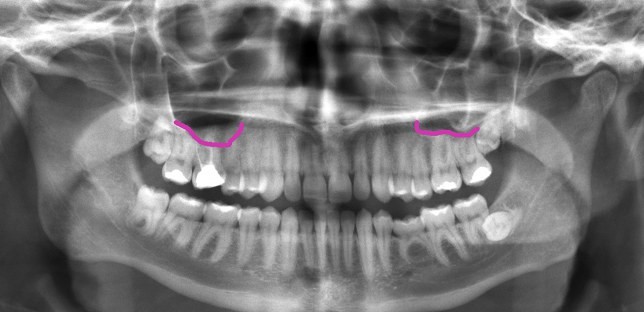

در زیر تصویر پرتوی ایکس از دهان را مشاهده میکنید که کف سینوس ماگزیلاری با خط بنفش مشخص شده است. سینوس درست بالای دندانهای بالایی قرار گرفته است بنابراین نزدیک ریشه دندانهای مولر (آسیاب) قرار دارد.

در سمت چپ به نظر میرسد کف سینوس، زیر ریشه دندانهای مولر بالا قرار گرفته است اما معمولا چنین نیست و این تصویر دو بعدی به خاطر هم پوشانی موقعیت ریشه دندان و سینوس به این صورت دیده میشود و در واقع یکی جلوتر و دیگری عقب تر قرار دارد.

در هر صورت با این تصویر به خوبی متوجه میشوید چرا عفونت سینوس میتواند با دندان درد اشتباه گرفته شود.